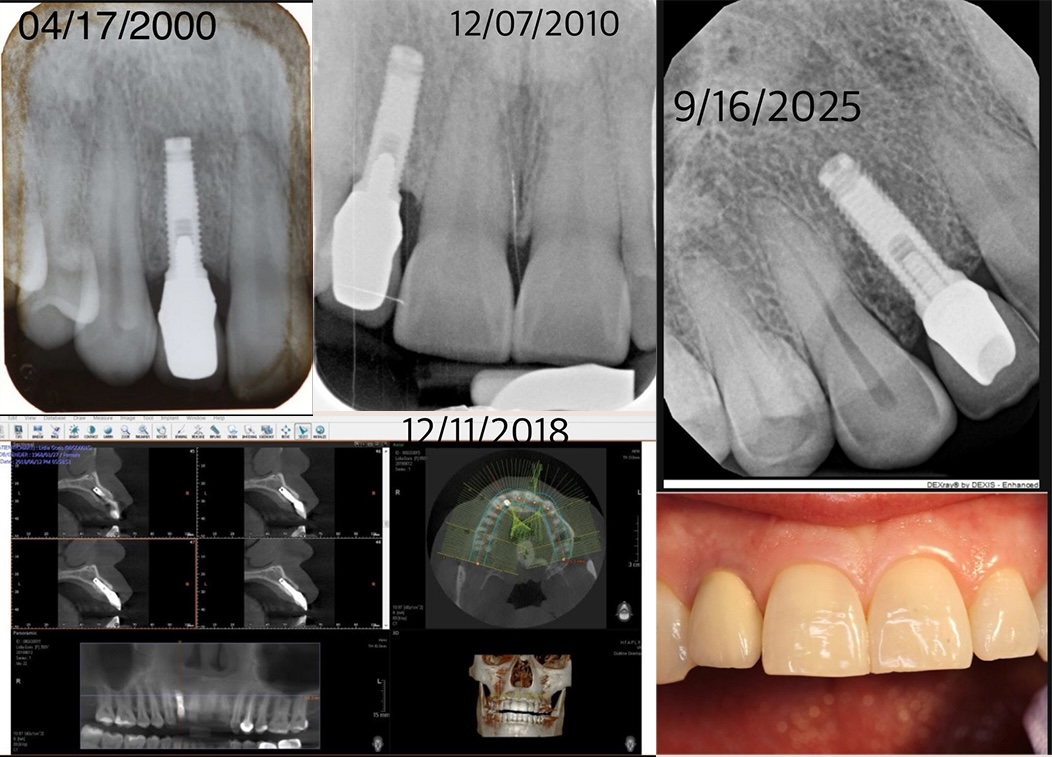

【大紀元2025年11月23日訊】(大紀元工商訊)在整理舊患者資料時,紐約實惠牙科(DC Dental)宋院長(Dr. Jun Song)意外翻出了一組特別的X光片——那是一位患者25年前接受的植牙紀錄。讓他驚訝的是,這顆植牙從當年手術、10年後複診、18年後的3D影像,到今日超過四分之一個世紀,始終穩固、健康、咀嚼力強,彷彿一顆近乎「永續」的假牙。

影像清楚顯示,這顆植牙不僅穩固如初,周圍的牙槽骨密度依舊緊密、沒有絲毫發炎或退縮跡象。10年後的X光片中,植體像一根穩穩立在山脊上的支柱;18年後的3D掃描更呈現周圍骨質均勻包覆,彷彿與天然牙根無異;而25年後的片子,則再次證明當年的角度與深度設計極為精準,使植體與口腔結構完美契合。「讓我欣慰的是,這顆植牙到現在還像新的一樣健康。」宋醫師說。「患者這些年來非常用心清潔,而我當年種植的位置也拿捏得非常準確。」這種準確度,正是植牙能走過25年的關鍵。

1996年,宋醫師從哥倫比亞大學牙科學院以四年全額獎學金畢業,1999年在哈佛大學牙醫學院完成牙周病專科訓練,成為美國牙科界極少數的韓裔專科醫生。如今踏入臨床第28年,宋醫師已邁入花甲之齡,他望著當年親手完成的植牙紀錄,感慨時間飛逝。回顧從醫生涯,他感慨地說:「牙科是一門技術,但醫師與患者之間的信任,卻是一門藝術。真正的實力,不在於你能多快完成手術,而在於10年、20年後,患者的牙齒是否依然健康。」這份25年的紀錄,對他來說是莫大的成就感與驕傲。